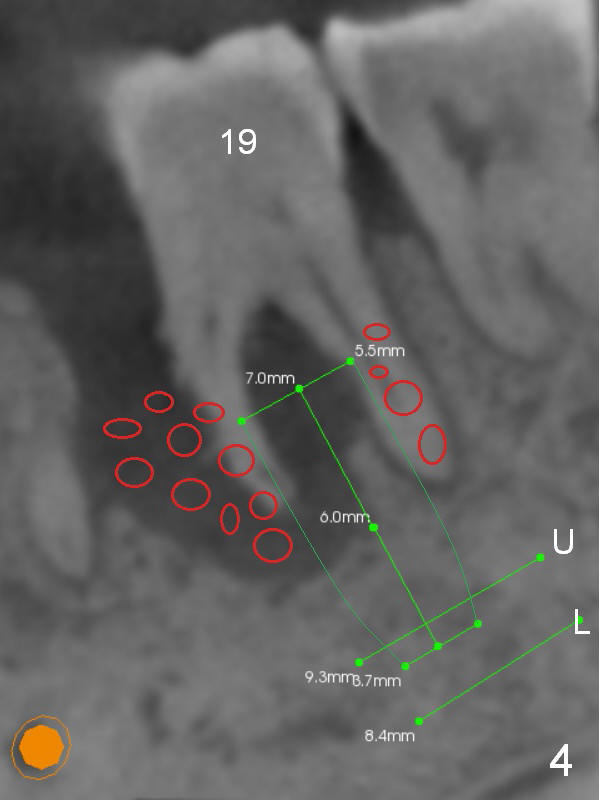

A 45-year-old man (SH) has periodontal (#3,9,19,23 (bone loss: Fig.1-3 *)) and orthodontic (#7,10 cross bite) problems, which he wants to solve at the same times. The tooth #19 is symptomatic (Fig.4,5). Infiltrate the buccal plate with 2% Xylocaine 1:50,000 Epinephrine and Septocaine (away from the Mental Foramen). After extraction and debridement, the socket is treated with Metronidazole. Osteotomy is initiated slightly buccal (B) to the middle of the socket bottom (Fig.5), using Sinus Master Kit drills (6 mm deep). After each drill, gently explore the lingual wall of the osteotomy with a fine curette or an explorer to determine whether the wall is perforated or not. Place a 5.5x13 mm implant (or short) between the buccal plate and the Inferior Alveolar Nerve (brown circle). If the torque is high, use the corresponding drill and tap. A 5.5 mm angled abutment will be used (15 or 25°, will arrive Monday morning). When X-ray is taken, the apex of the osteotomy should be superior to the upper border of the Inferior Alveolar Canal (Fig.4 U) and inferior to the Lower one (L). Bone graft is placed (Fig.4,5 red circles) after placement of PRF buccally (Fig.5 yellow curved line). If visibility is poor, make an incision and insert Epinephrine gauze under periosteum for hemostasis. Take photos when a 2 mm pilot drill in place to show the coronal end of the drill at the lingual cusp instead of the central fossa.